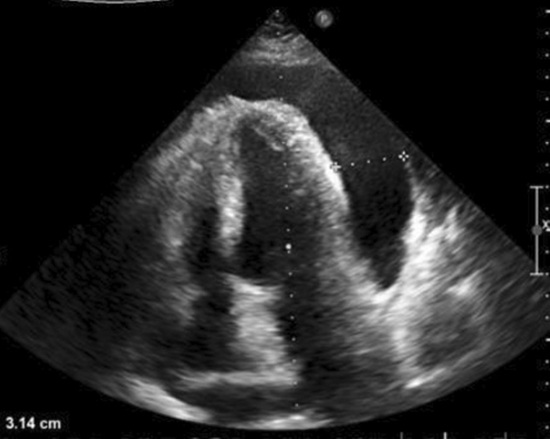

مرد ۶۰ ساله با سابقه ۵ ساله هپاتیت خودایمنی و سیروز کبد، با تنگی نفس شدید، درد سینه، بیقراری و ورم بدن (افزایش ۴ کیلوگرم وزن) به اورژانس آمد. علائم: زردی پوست، صدای خفه قلب، فشار خون ۱۱۰/۷۰، ضربان ۱۱۰ ضربه در دقیقه. آزمایشها: مشکلات شدید کبدی-کلیوی، قند خون بالا (۴۹۲). تصاویر: ۱۱۰۰ میلیلیتر مایع اطراف قلب.